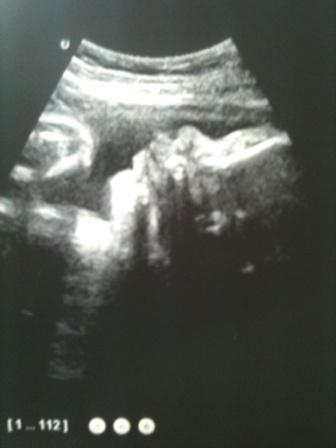

а это мы

нам по месячным 13 и 4, по узи на 8 дней больше

Оль, там где малыш на коленках, вообще классный кадр. ну это ж надо такой момент